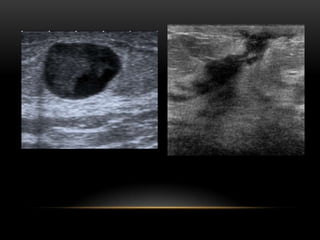

Nódulos (ecografía)

Forma Ovalada Redondeada Irregular Orientación Paralela No paralela Márgenes Circunscritos No circunscritos Límitesde la lesión Interfase abrupta Halo ecogénico Patrón ecogénico Anecogénico Hiperecogénico Complejo Hipoecogénico Isoecogénico Hallazgos acústicos posteriores Sin hallazgos posteriores Refuerzo posterior Sombra acústica Mixto Nódulos (ecografía)